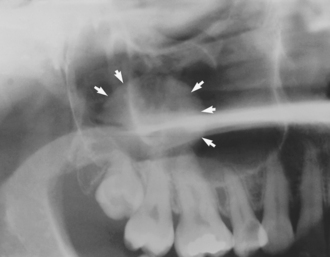

Antral mucosal cysts are frequently discovered as incidental findings on dental radiographs (Fig. 15.8). They are generally symptomless and have no long-term significance, but care should be taken to differentiate between truly antral lesions and cysts of odontogenic origin (apical cysts, dentigerous cysts and odontogenic keratocysts), which do require treatment.

Fig. 15.8 A benign antral mucosal cyst (arrows) may be an incidental finding on a dental radiograph.